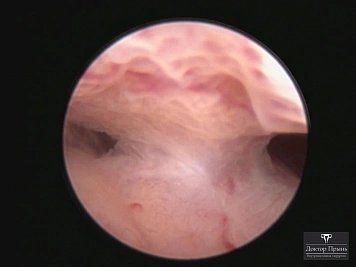

Фотогалерея

Синехии, рассечённые Прынь Д.В.